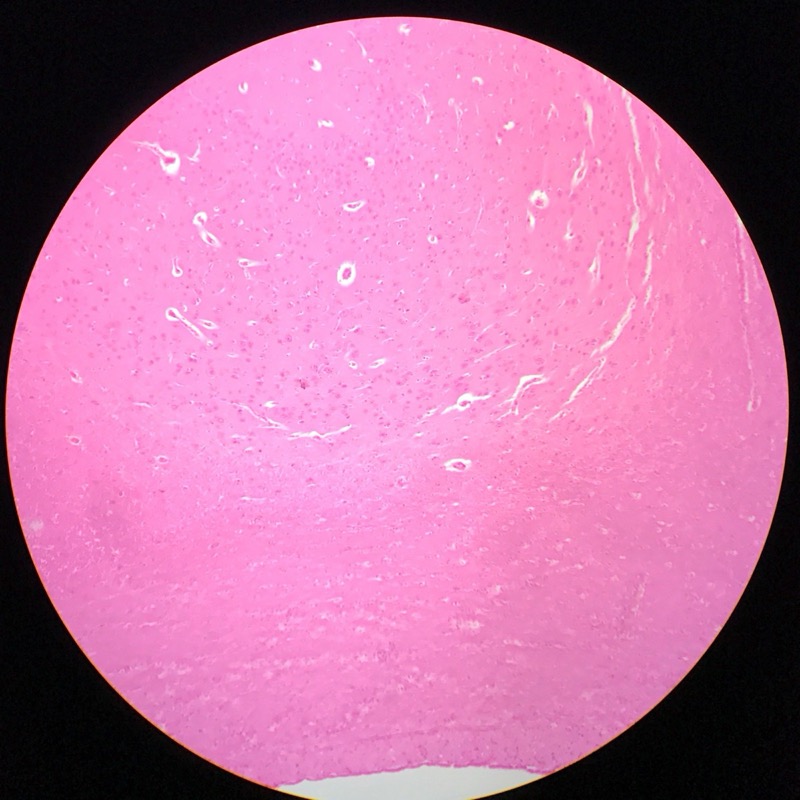

| 1:8:5 | Medulla Spinalis Galiomycin/Azan | ![]() ![]() ![]() ![]() |

| 1:8:6 | Medulla spinalis, silverfärning | ![]() ![]() ![]() ![]() ![]() ![]() |